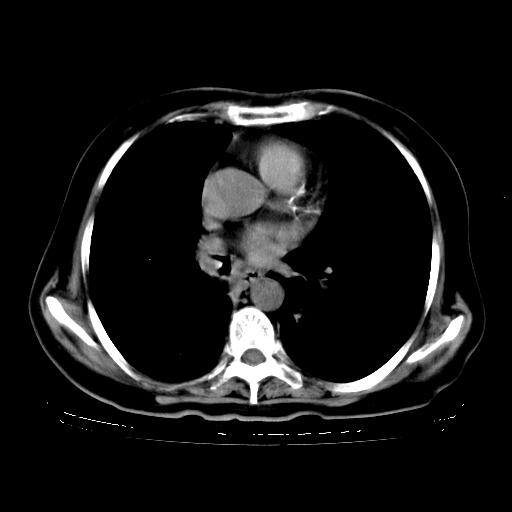

女,70岁,咳嗽、咳痰一个月,低热一周。

1.左上肺结核,部分纤维化。右肺中下叶部分肺不张,内见液化、坏死及点状钙化,右中下叶支气管壁增厚、管腔狭窄,见多个点状钙化,结合临床考虑支气管内膜结核,建议痰检查抗酸杆菌并参考血沉。两肺多个小圆点状高密度灶,境界模糊,多考虑结核肺内播散。但本人年龄较大首先应支气管镜检以除外右肺癌。

2.胸主动脉夹层。

1、右肺占位,考虑周围型ca 。

2、右下肺软组织密度肿块影,考虑肺隔离征。

3、两肺肺结核(右肺下叶背段及左肺)。

4、主动脉夹层。

5、右侧少量胸腔积液。